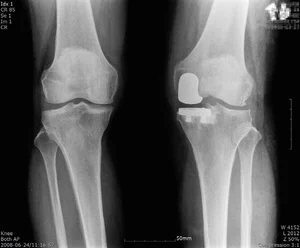

퇴행성관절염 말기 환자 위한 로봇인공관절 수술, 정밀성과 안전성 높여

“계단을 오르내릴 때마다 무릎이 쑤시고, 조금만 걸어도 무릎이 붓는다”는 말기 퇴행성관절염 환자들의 호소는 낯설지 않다. 노화로 인한 관절 손상은 물론, 비만과 생활습관 등의 요인으로 발병 연령이 점점 낮아지면서 무릎 통증으로 고통을 겪...

퇴행성관절염은 무릎 관절 연골과 인대가 손상되며 발생하는 질환으로, 노화와 무리한 사용이 주된 원인이다. 초기에는 물리치료, 약물치료 등 보존적 치료로 관리할 수 있지만 질환이 말기까지 진행되면 관절 연골이 거의 소실되고 통증과 변형이 심해져 인공관절수술이 필요하다. ...

자기관절 보존하는 ‘인공관절 부분치환술’...정밀한 삽입 위치 선정 중요

퇴행성관절염은 65세 이상 노령층에서 흔하게 발생하는 질병이다. 주로 노령층에서 발병하지만 중년 이후부터는 특별한 외상이 없어도 관절이 붓고 아픈 증상이 있다면 의심할 필요가 있다. 일반적으로 관절을 보호하는 연골이 손상되거나, 노화에 따른 퇴행으로 닳아 없...

연세사랑병원 "야외활동 봄철시즌…무릎 관절염 말기에 한국형 인공관절"

야외활동이 늘어나는 봄철, 경로당에서 삼삼오오 모여 가벼운 나들이부터 등산을 준비하는 어르신들이 많다. 추운 겨울 동안 움직임이 적어진 근육과 관절은 갑작스러운 활동량 증가에 무릎에서 소리, 열감 등 통증을 호소한다. 이는 대표적인 퇴행성관절염 증상으로 관절 건강에 주...

쪼그려 앉는 자세가 통증 유발...‘한국형 인공관절’ 치료

농사를 업으로 삼는 사람부터 취미로 텃밭을 가꾸는 사람까지 봄은 신선한 작물을 직접 키우는 이들에게 중요한 시기다. 다만, 밭일이나 나물을 채취하는 작업은 오랫동안 같은 자세로 무릎을 쪼그려 앉거나 허리를 구부려서 근골격계에 무리를 주는데 이에 따른 대표적인 질환이 &...